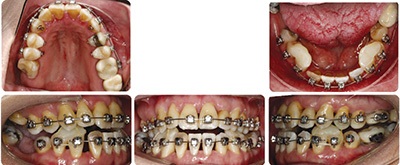

Instead, the turbos were placed on the lower canines and first bicuspids. These teeth, and the maxillary canines that would abut them, showed relatively good periodontal support and longer roots. They could likely shoulder the concentrated masticatory load in this periodontally compromised patient for more than a few months of treatment if needed. Also the turbos were shaped into a ramp (they sloped in to the lingual) to give function to their form. As the maxillary canines (which were in crossbite) hit the ramps, there would be a labial crown-tipping effect to jump their position out of crossbite as the maxillary teeth aligned. Crossbite elastics also played an important role in this regard as well.

Another important strategy was to use early interproximal reduction (IPR) in multiple stages during alignment of the maxillary crowding. While it was expected that Shelley’s dark triangles would not be able to be corrected with our treatment (her anterior papillas were almost completely gone), early IPR has been shown to limit “round-tripping” and minimize the unfavorable dark triangle potential.

Despite significant IPR throughout treatment, these dark triangles are still obvious in her final smile. I was tempted to continue with further IPR for aesthetic reasons but here is my rationale for not doing so. In order to decrease the most aesthetically prominent dark triangles, which are in her maxillary anterior teeth, I would need to also perform more IPR in her lower anterior teeth to allow the overjet to couple appropriately. Remember that Shelley’s lower incisors were the teeth that were of greatest periodontal concern at the start of treatment. The lower incisors were also in a slightly more compensated/upright position to begin with in her forward mandible. When I closed her pre-existing mandibular anterior spaces these teeth uprighted a bit more. When I performed IPR throughout treatment on the lower anterior teeth to minimize the dark triangles and then closed those spaces, these teeth uprighted a bit more again. You can see the change in angulation of these teeth when comparing pre to posttreatment ceph images. Despite my distaste for dark triangles in the smile, I did not think it wise to further decrease the labiolingual inclination of these teeth any further with continued IPR.